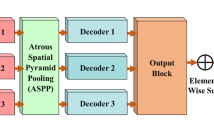

Automatic multimodal image segmentation is considered a challenging research area in the biomedical field. U-shaped models have led to an enormous breakthrough in a large domain of medical image segmentation in recentyears. The receptive field plays an essential role in convolutionalneural networks because too small a receptive field limits context information, and too large loses localization accuracy. Despite outstanding overall performance in biomedical segmenting, classical UNet architecture uses a fixed receptive field in convolutions operations. This study proposes a few modifications in classical UNet architecture by adjusting the receptive field via feature-fused module and attention gate mechanism. Compared with baseline UNet, the numerical parameters of FF-UNet (3.94 million) is 51% of classical UNet architecture (7.75 million). Furthermore, we extended our model performance by introducing post-processing schemes. The tri-threshold fuzzy intensification-based contrast enhancement technique is utilized to improve the contrast of biomedical datasets. In the second tier, the black top-hat filtering-based method is employed to remove hair-like artifacts from the ISIC 2018 skin lesion dataset, which may create a barrier to correctly segmenting the images. The proposed models have been trained using fivefold cross-validation on five publicly available biomedical datasets and achieved the dice coefficients of 0.860, 0.932, 0.932, 0.925, and 0.894 on ETIS-LaribPolypDB, CVC-ColonDB, CVC-ClinicDB, DSB 2018, and ISIC 2018 datasets, respectively. To further verify our claims, comparative analysis based on dice results is conducted, proving the proposed model effectiveness. The FF-UNet implementation models and pre-trained weights are freely publicly available: https://github.com/ahmedeqbal/FF-UNet.